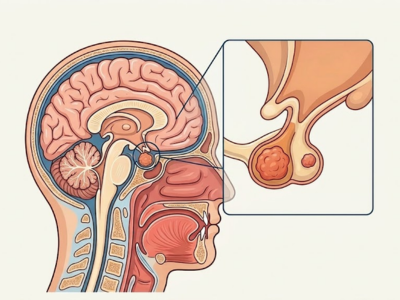

Pituitary Tumors

Tumors that grow in the pituitary gland, which controls hormone production.